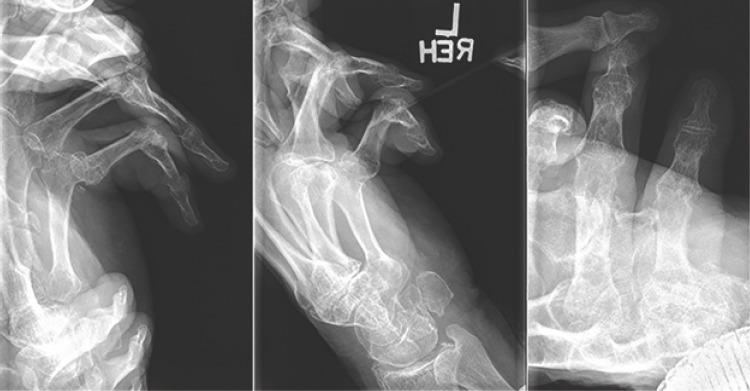

The patient is an 80-year-old right-hand dominant retired male with bilateral hand contractures and palmar fibromatosis. His medical history is notable for Type II diabetes mellitus and metastatic thyroid cancer. The patient underwent Xiaflex injection of the left small finger and returned 4 days later for planned release. An appreciable release of the contracture was noted; however, there was a concern for plastic deformation of the proximal phalanx as a result of the manipulation. X-rays confirmed the fracture and apex volar angulation at the base of the proximal phalanx. The fracture appeared amenable to non-operative treatment. The patient has been followed closely and has had no pain or tenderness at the fracture site and minimal swelling. X-rays at 1 week and 1 month showed maintained alignment and signs of consolidation at the fracture site. The patient is currently 4-month post-fracture, and no further intervention has been pursued.